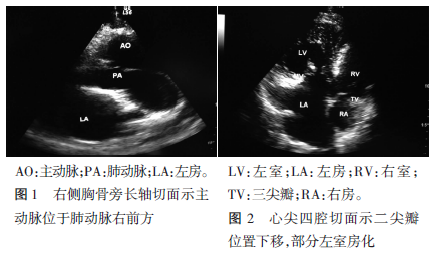

右位心完全性大动脉转位伴二尖瓣下移超声表现1例